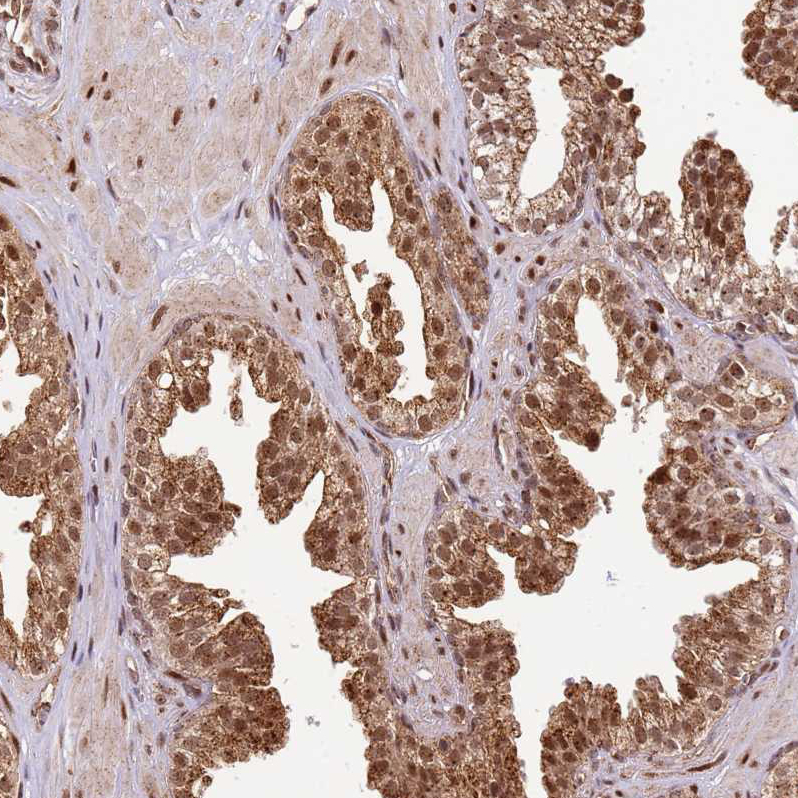

Immunohistochemical staining of human prostate shows strong cytoplasmic positivity in glandular cells.